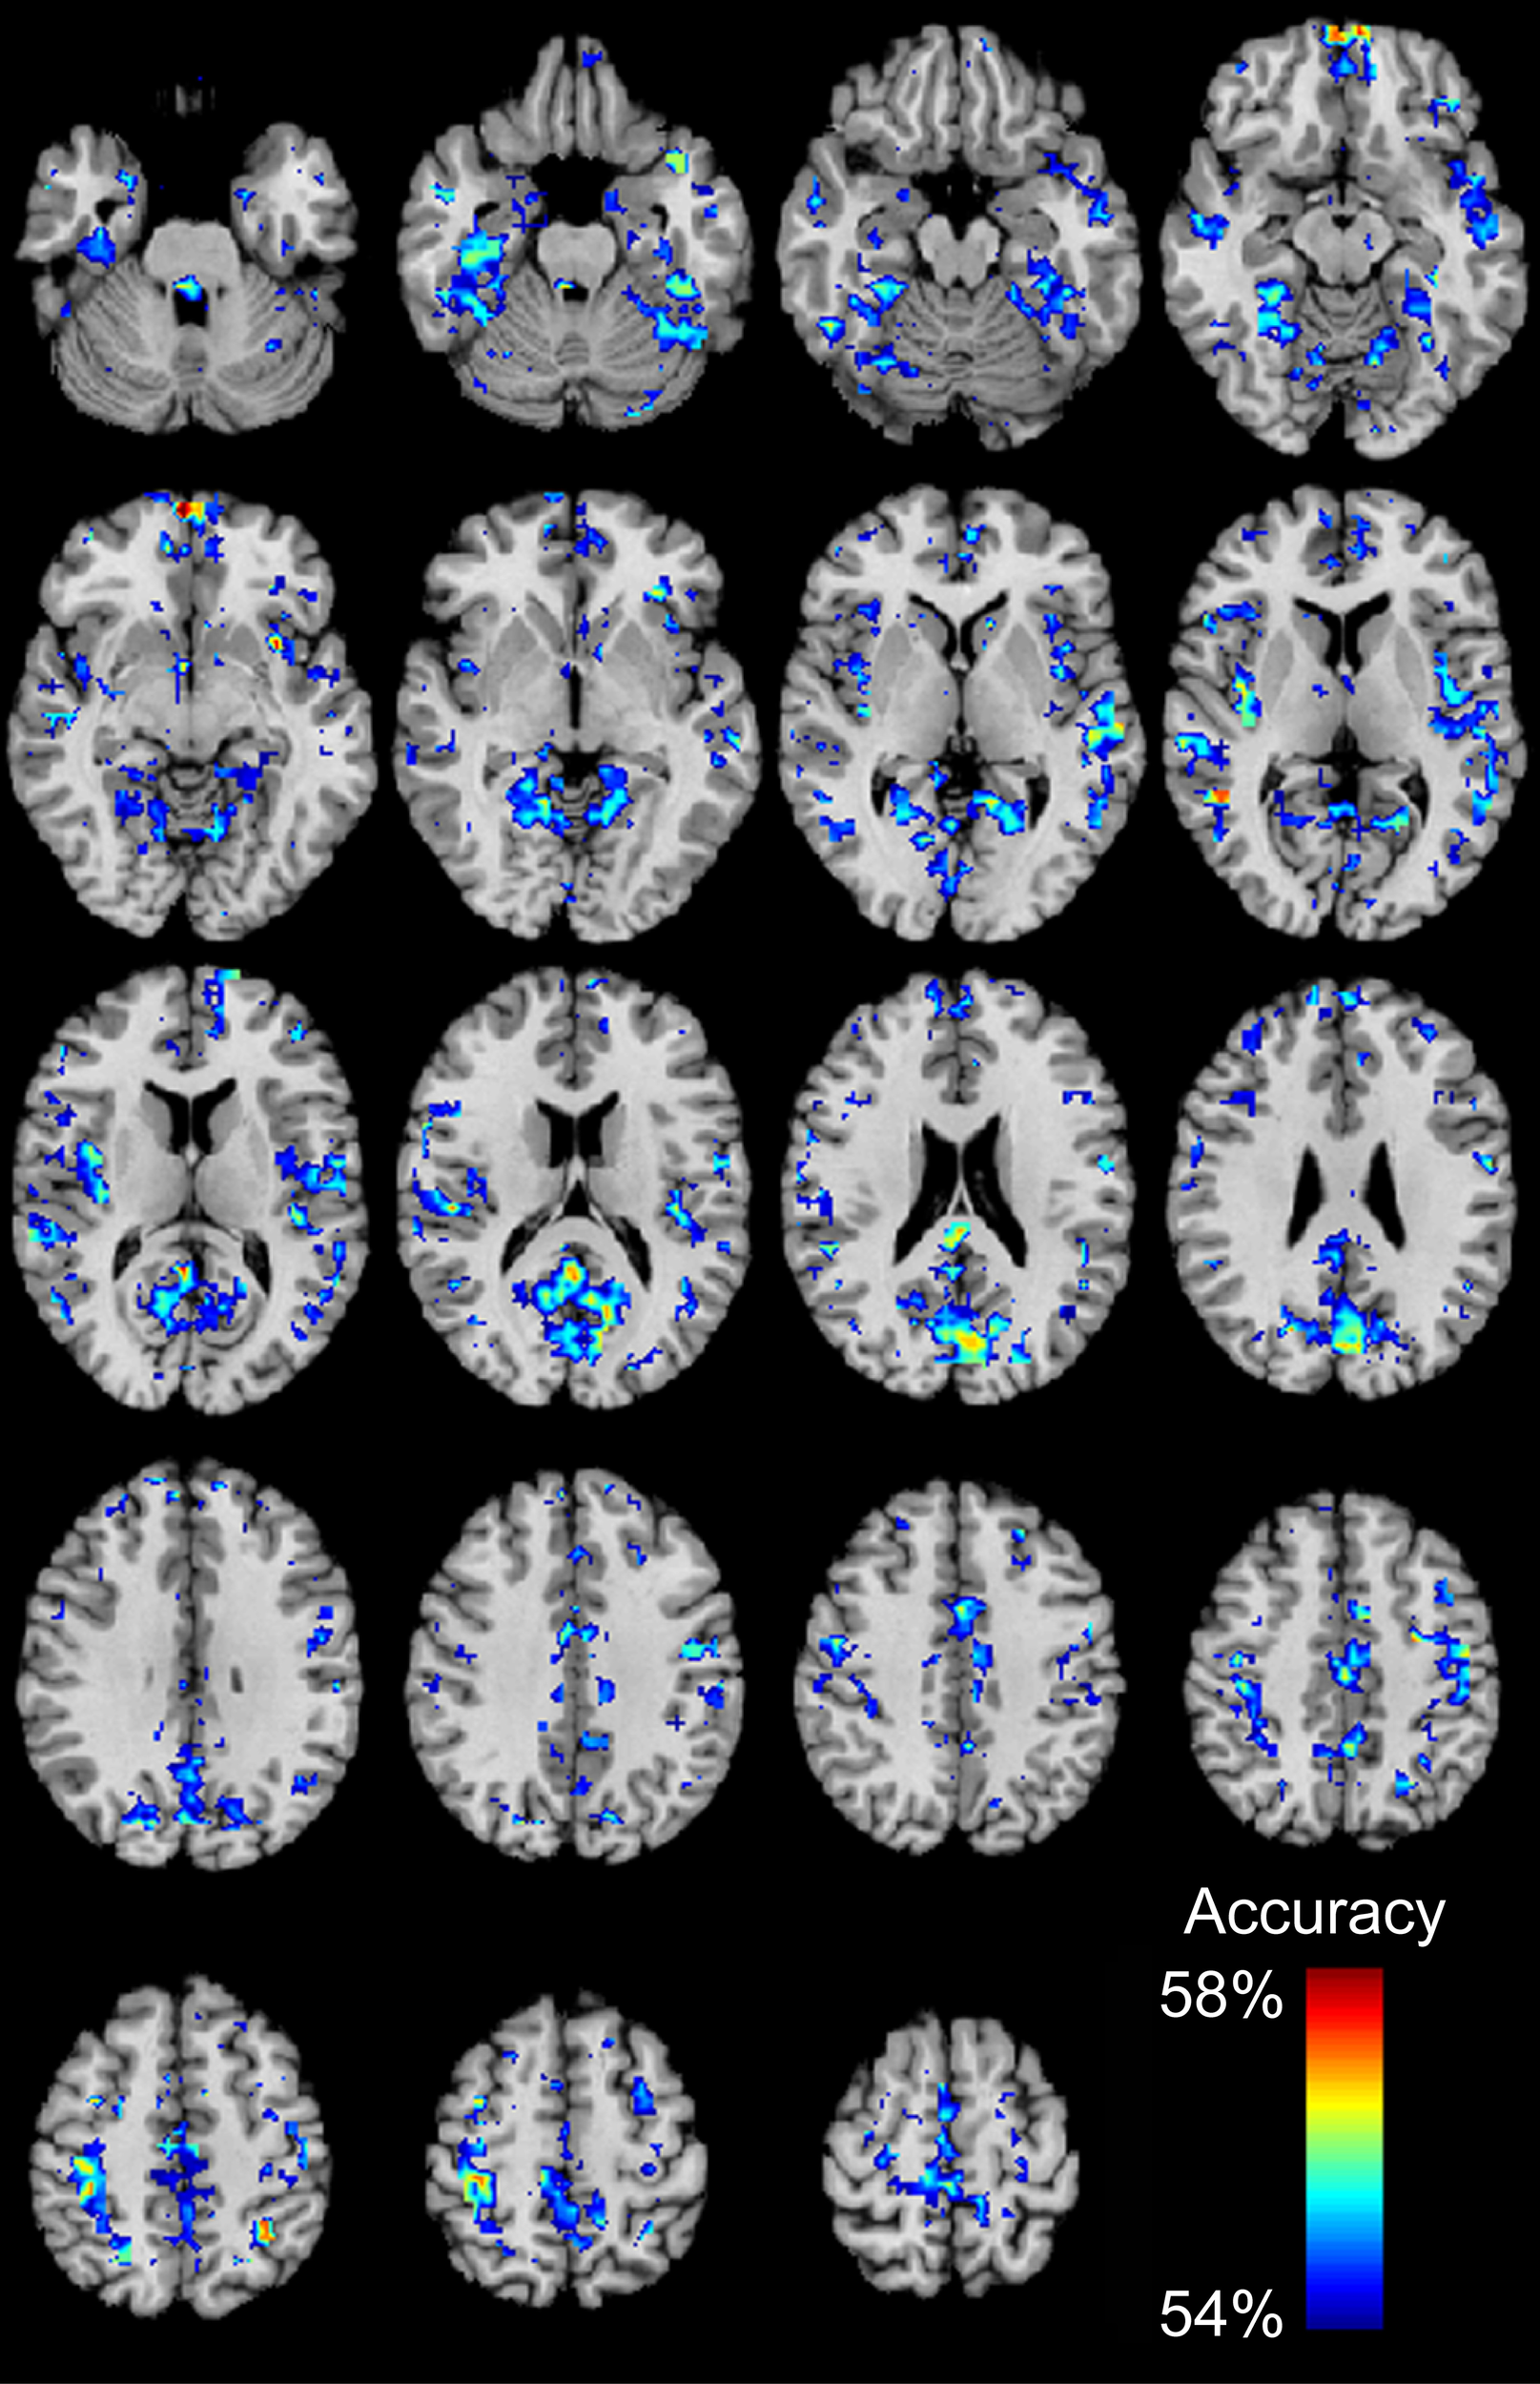

We then determined which brain regions and connection characteristics accurately classified the ABIDE subjects. In Figure 5, the following brain regions (and the 7265 connections in which they were involved) resulted in the highest accuracy: parahippocampaland fusiform gyri, insula, medial prefrontal cortex, posterior cingulate cortex, Wernicke Area, and intraparietal sulcus. In Figure 6, two clusters of bins resulted in the highest accuracy. The first cluster included bins with short-range (10–25 mm) and medium-strength connections (0.3 < z < 0.5). The second cluster included bins with long-range (100–125 mm) and medium-strength connections (0.15 < z < 0.4).

Figure 5

Total accuracy for 7266 brain regions. Accuracy was determined for each of the 7266 brain regions independently by only taking into account the 7265 connections in which a given region was involved (no p-value threshold, all connections used). The minimum accuracy displayed for a single region is 53.95%, which was the false discovery rate corrected percentage for 7266 regions and a binomial cumulative distribution.